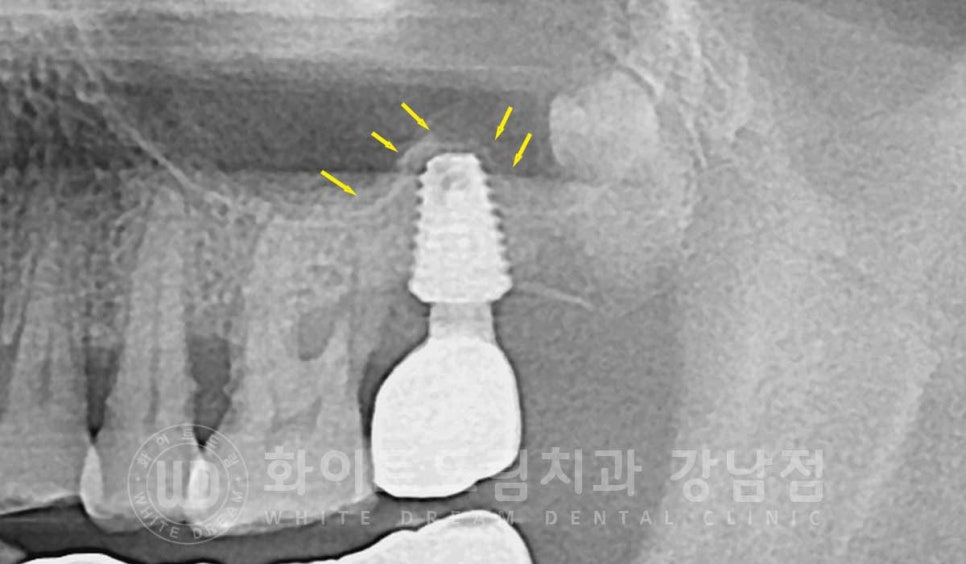

▲ 크라운 뿌리가 부러져있고 내부 염증이 심하게 생겨 잇몸뼈가 많이 녹은 상태입니다.

이미 치아를 더 이상 살릴 수 없을 정도로 심하게 흔들리고 있었고

잇몸뼈도 염증으로 심하게 녹은 상태였기에 이 크라운은 모두 제거 후

임플란트를 식립하기로 환자분과 상의 후 결정되었습니다.